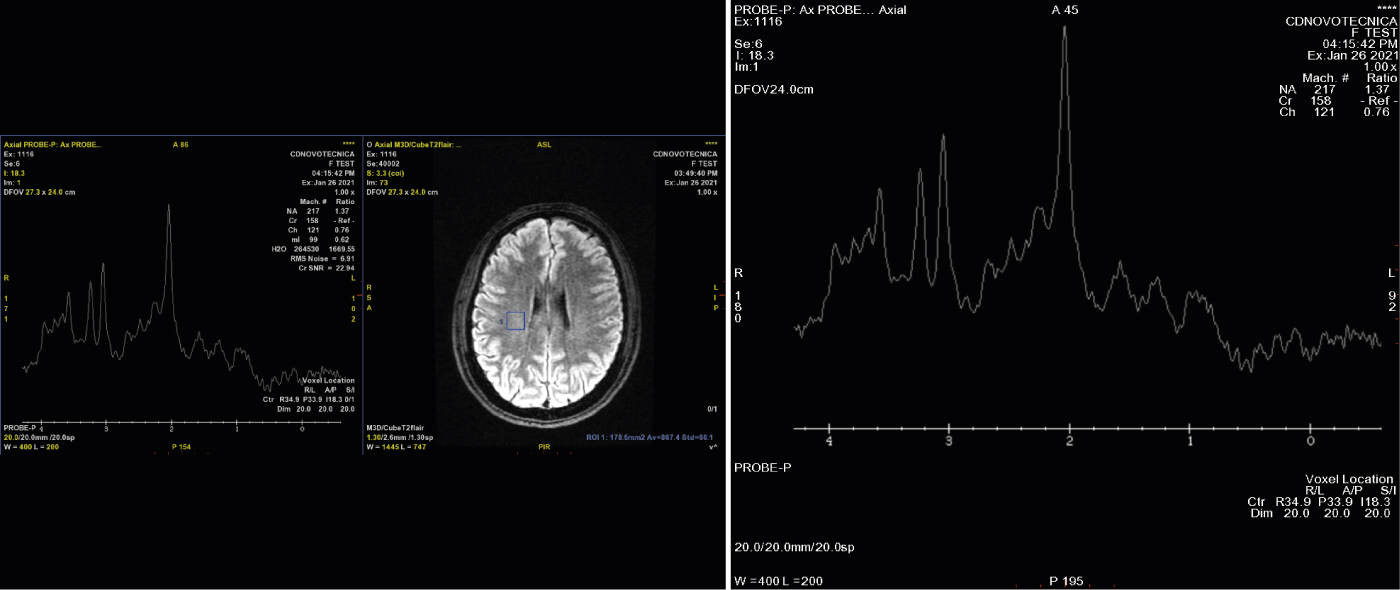

ESPECTROSCOPIA

Analizamos los metabolitos, que son distintas sustancias simples producidas en reacciones metabólicas en el organismo. Por ejemplo, lo que denominamos marcador neuronal es el N-acetil aspartato, que es abundante en sustancia gris; la colina, es un marcador de las membranas celulares. Se estudian los metabolitos “per se” y también la relación entre ellos.

Las indicaciones fundamentalmente de la espectroscopia por RM son ayudar en el diagnóstico diferencial entre lesiones benignas y malignas, especialmente cerebrales; dentro de las malignas el objetivo es intentar distinguir distintos tipos de cánceres. Patologías con similar apariencia en Resonancia podrían distinguirse a través de la espectroscopia, aportando información adicional en el diagnóstico. Permite hacer estudios de seguimiento de lesiones, por ejemplo, tras radioterapia en el cerebro.

Univoxel

Multivoxel